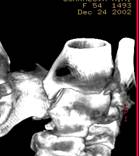

При выявлении на МРТ костных изменений, следующим этапом диагностического поиска являлось использование КТ, а также 2 и 3D реконструкции полученных данных.

|

| Рис 8. СРКТ HiSpeed с шагом томографа 3 мм и 3D реконструкция. По передне-наружной поверхности (стрелка) большеберцовой кости визуализируется свободнолежащий костный отломок размером 15х15.4х7.2 мм. а – малоберцовая кость. б – большеберцовая кость. |

Рис 12. Выявлено: по внутренней поверхности таранной кости дефекты в виде наличия полостей овальной конфигурации, с четкими плотными краями (стрелки). СРКТ HiSpeed с шагом томографа 3 мм |

Для оценки степени распространенности процесса в костной ткани произведена КТ.